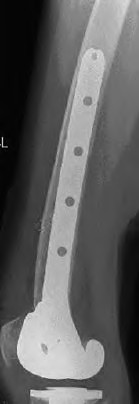

Question 51

A patient requires a femoral revision THA for aseptic loosening. Radiographs demonstrate extensive metaphyseal bone loss with the diaphyseal cortical bone remaining fully intact for only 3 cm distal to the tip of the current stem. According to the Paprosky femoral defect classification, what type of defect is present?